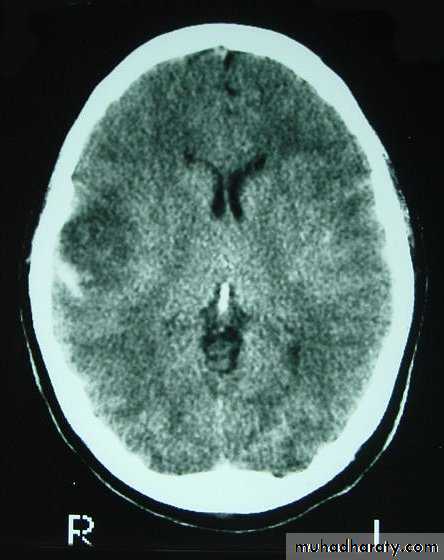

1. Brain Oedema (Cerebral Swelling)

Can be local (around a haematoma) or diffuse.

It is due to intracellular or extracellular accumulation of fluid.

It leads to raised intracranial pressure, which itself causes problems.

It is more common and more dangerous in children.